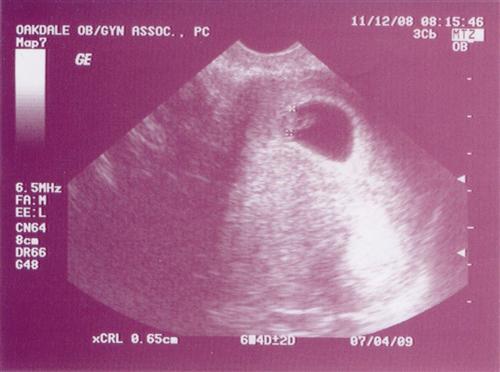

6 weeks